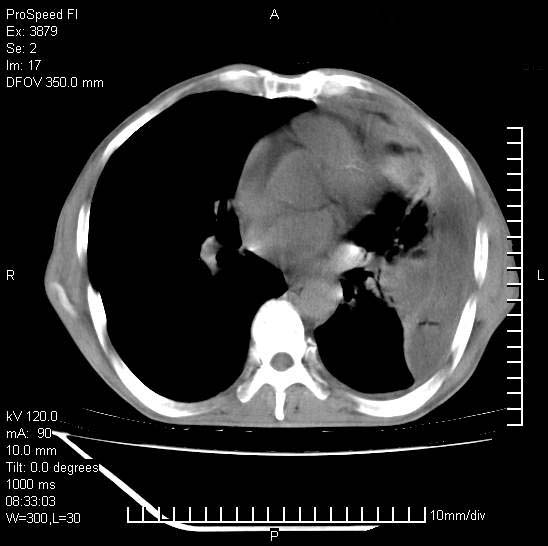

以下是引用37度在2008-6-6 11:20:00的发言:[br]1.包裹性积液,多考虑结核性;[br]2.穿刺术后改变。

以下是引用312nanyang在2008-6-6 15:12:00的发言:[br]基本支持楼主意见[br]疑问?左下肺支气管旁的软组织(16层)密度怎么解释?淋巴结还是斜裂胸膜增厚所致?能否增强进一步检查